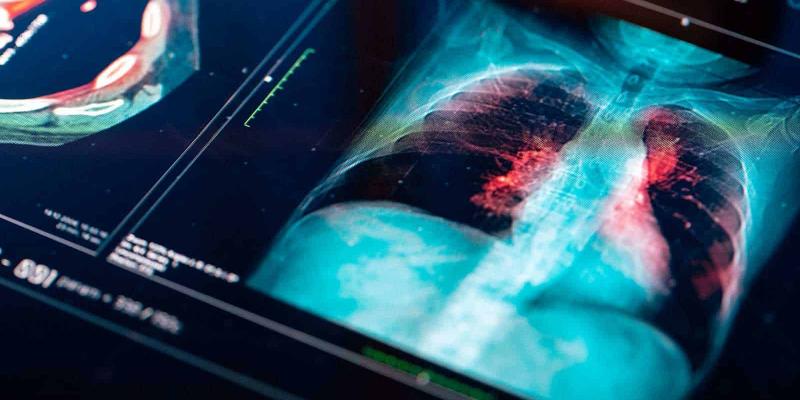

Una nueva investigación por parte del Grupo Español de Cáncer de Pulmón (GECP) ha logrado modificar la manera de abordar los tumores de cáncer de pulmón en estadios iniciales, es decir, sin metástasis. Esta nueva estrategia ha logrado favorecer hasta al 93 % de los pacientes candidatos a cirugía, además de erradicar y favorecer el proceso de curación del tumor.

Este grupo de científicos españoles ha conseguido aumentar hasta el 36,8 % el número de pacientes que consiguen disminuir de manera completa el tumor, en comparación al enfoque tradicional. Esta nueva investigación científica irá dirigida a los pacientes que sufran tumores de pulmón en estadios iniciales, sin metástasis, por lo que el porcentaje de pacientes aumenta.

El estudio NADIM II, con 86 pacientes de distintos hospitales españoles, ha probado antes de la cirugía un tratamiento combinado de quimioterapia e inmunoterapia en un grupo de pacientes y lo ha comparado con otro tratado solo con quimioterapia, pero todos ellos se han visto más avanzados en el estudio IIIA.

Según los resultados, el 93 % de los pacientes con con este tipo de cáncer que recibieron quimioterapia e inmunoterapia pudieron optar a la operación, frente al 69 % de los tratados solo con quimioterapia.